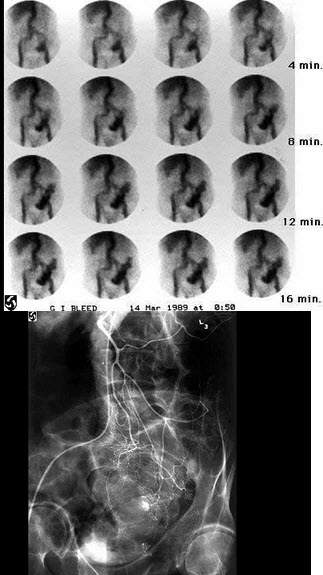

71岁女性,突发鲜血便5小时,急诊行99Tcm-RBC消化道出血显像如图,随后行选择性肠系膜动脉血管造影术如图,诊断是()

A.横结肠出血

B.空肠出血

C.回肠出血

D.乙状结肠出血

E.以上都不是